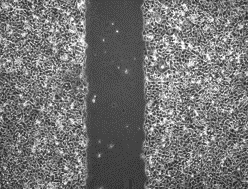

Xác minh sơ bộ PIXCELL BIOM™

Kết quả được chứng minh trong phòng thí nghiệm là nhanh hơn 56% so với lipid da trung bình *

* Kiểm tra xem độ dài ở giữa hẹp đến mức nào.

- Trước khi sử dụng chất thử nghiệm

- 12 giờ sau khi dùng chất thử

Bảng 1. Tốc độ thay đổi tế bào theo thời gian

Nội dung thử nghiệm

Sau khi dùng chất thử nghiệm cho đối tượng thử nghiệm nhận được kích thích trung tâm và quan sát trong 12 giờ, tỷ lệ thay đổi 75,8% đã được xác nhận

ở đối tượng thử nghiệm được dùng PixelBiome™ .

*Là một thí nghiệm nội bộ để giúp hiểu rõ hơn, những điều trên chỉ giới hạn ở tính chất của nguyên liệu thô.